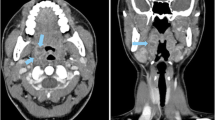

Figure 6 shows a comparison between a CT image acquired with the reference protocol and three CT images illustrating the effects of different parameter combinations: (1) acquired with reduced tube current (TCM SD 14) and reconstructed with AIDR 3D, (2) acquired with reduced tube voltage (100 kVp) and reduced tube current (TCM SD 14) and reconstructed with AIDR 3D, and (3) the same acquisition parameters as in (2) but reconstructed with FBP. A higher TCM noise level resulted in inferior detectability when combined with 120-kVp tube voltage while detectability was unchanged when combined with a reduced tube voltage of 100 kVp. Likewise, image reconstruction with FBP at reduced tube voltage and higher TCM noise level resulted in inferior detectability while reconstruction with AIDR 3D did not (Table 2).

CT images illustrating the effects of tube voltage reduction, tube current reduction, and the image reconstruction method used. a Reference protocol (120 kVp, TCM SD of 7.5, pitch of 0.813, AIDR 3D). b Reduced tube current (120 kVp, TCM SD of 14, pitch of 0.813, AIDR 3D). c Reduced tube voltage and tube current (100 kVp, TCM SD of 14, pitch of 0.813, AIDR 3D). d Same acquisition parameters as c but reconstructed with FBP instead of AIDR 3D. The drawing indicates the lesion position, and lesions are additionally indicated by white arrows in the CT images. Images are displayed with window level/window width 40/350 at 120 kVp and 80/350 at 100 kVp

These results were consistent with the results obtained with other parameter combinations. In a comparison across all protocols, a TCM noise level increase from 7.5 to 14 reduced detectability at 120-kVp tube voltage (AUC 0.821, 95% CI: 0.802 to 0.840 vs. 0.776, 95% CI: 0.757 to 0.795; p = 0.003). However, at 100 kVp, detectability was less markedly degraded by a TCM noise level increase from 7.5 to 14 (AUC 0.839, 95% CI: 0.820 to 0.858 vs. 0.819, 95% CI: 0.800 to 0.837; p = 0.354) and decreased only significantly in conjunction with a pitch of 1.388 (AUC 0.871, 95% CI: 0.839 to 0.904 vs. 0.789, 95% CI: 0.756 to 0.821; p = 0.001). Compared with FBP, AIDR 3D improved detectability at 100 kVp (AUC 0.806, 95% CI: 0.791 to 0.821 vs. 0.854, 95% CI: 0.838 to 0.869; p < 0.001), but not at 120-kVp tube voltage (AUC 0.793, 95% CI: 0.777 to 0.808 vs. 0.795, 95% CI: 0.780 to 0.810; p = 0.822). Conversely, lowering the tube voltage from 120 to 100 kVp significantly improved detectability with the use of AIDR 3D (p < 0.001), but not with FBP for image reconstruction (p = 0.226). These findings are summarized in Tables 3 and 4.